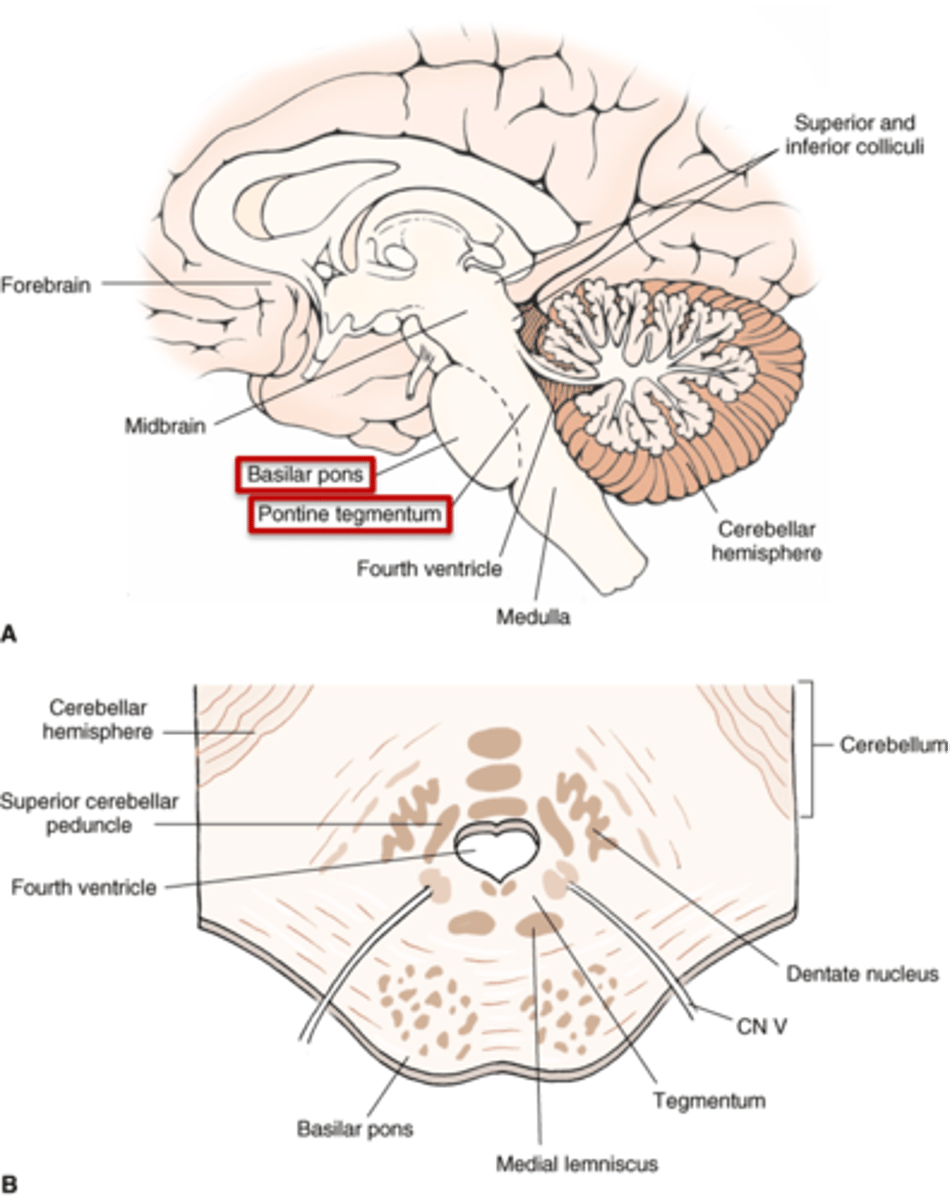

what are the 4 areas that the brainstem can be divided into (from posterior to anterior)?

1. tectum

2. ventricular system

3. tegmentum

4. basal portion

which area of the brainstem is the roof over the ventricular system?

tectum

which area of the brainstem makes up the core of the brainstem?

tegmentum

which area of the brainstem is situated most anteriorly?

basal portion

what are the 2 components that make up the ventral and dorsal area of the pons?

1. basilar pons (ventral)

2. tegmentum (dorsal)

what component of the pons forms the floor of the fourth ventricle?

tegmentum